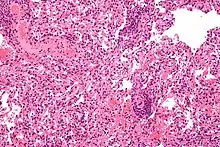

Doctors are patients are sometimes hesitant to accept organs from people who died of brain tumours. However, an analysis of the UK donor registry found no evidence of cancer transmission across more than 750 donations, including people with high-grade tumours. This suggests that it may be safe to increase the use of organs from people who died of a brain tumour, which could help reduce organ shortfall.[208][209]